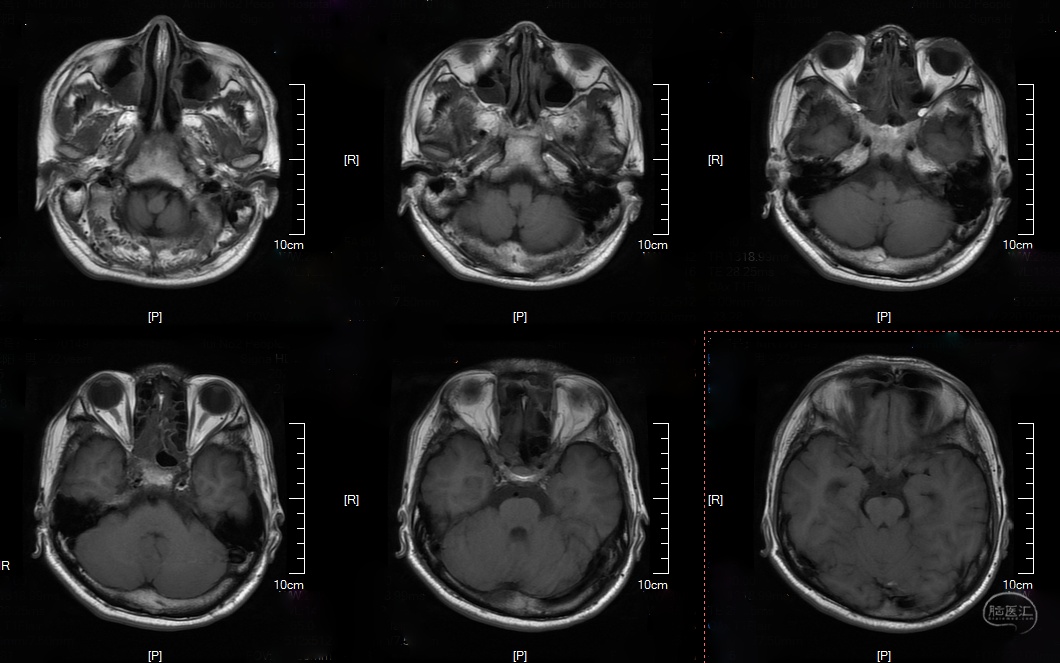

头颅CT及MRI:

DWI:

T2:

T1:

T2 flair: